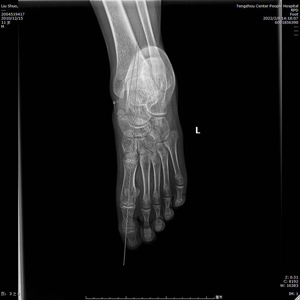

術中C型臂透視見:制動器位置良好,模擬左足負重試驗,患者足弓恢復良好。整個手術時間短,創傷小,見效快,僅用時30分鐘,微創刀口1cm,出血量不足5ml。術后左足石膏固定,2天后出院。?

(術后X線)